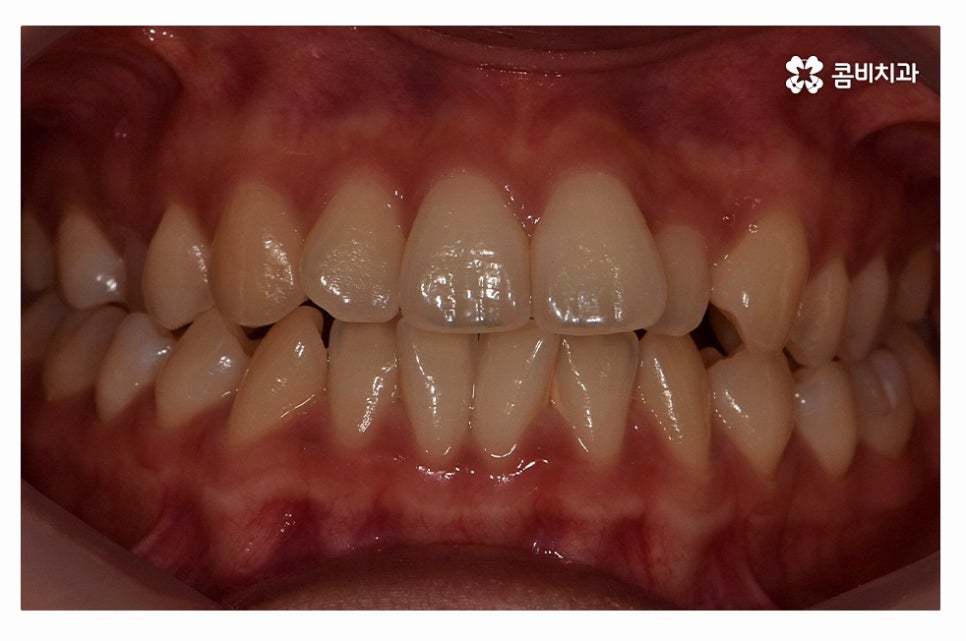

오늘 보여드릴 사례도 덧니교정이 비발치로 진행이 된 사례이며

치아의 이동 공간과 치아 상태, 골격, 얼굴형 등을

종합적으로 판단할 때 비발치로도 진행이 가능했던 사례라고 할 수 있어요.